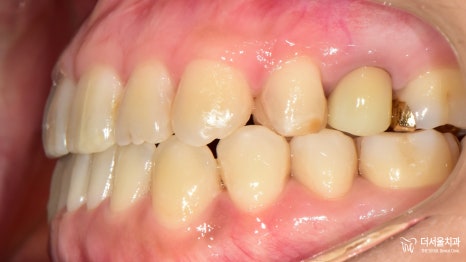

『이렇게 진료를 돕기로 했습니다.』

더서울에서는 겉으로 티 나는

브라켓, 와이어가 신경 쓰이는 환자분을 위해

투명장치인 인비절라인 을 사용하여

툭 튀어나온 주걱턱을 개선하기로 했습니다.

이때 이동할 공간이 필요했는데요.

# 48 사랑니 발치 후

그 공간을 이용하기로 계획을 세웠습니다!

좀 더 자세히 알아보자면,

양쪽 아래 치아를 최대한 뒤로 보내서

정상적으로 물리게끔!

즉, 윗니가 아랫니를 덮을 수 있도록

마무리를 도와드리기로 했습니다.